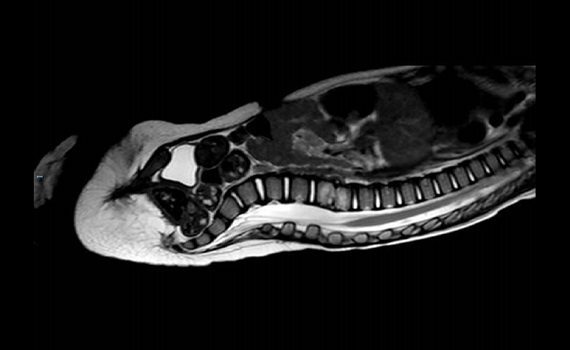

Manejo del lactante con estridor